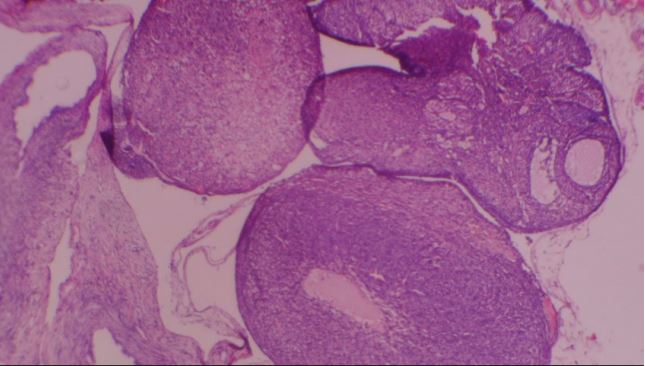

Figure 1: Photomicrographs of Ovary. Control. Composed of: A. coelomic epithelium, B. vascular sized stroma and follicles in different stages of maturation: C. graffian, D. secondary and E. primary (H&E x40).

Figure 2: Photomicrograph of ovary of Wistar rat given 40 mg/kg VCD only showing: A. graffian follicle, B. extruded follicle, C. active stromal congestion and D. primordial follicles (H&E x40).